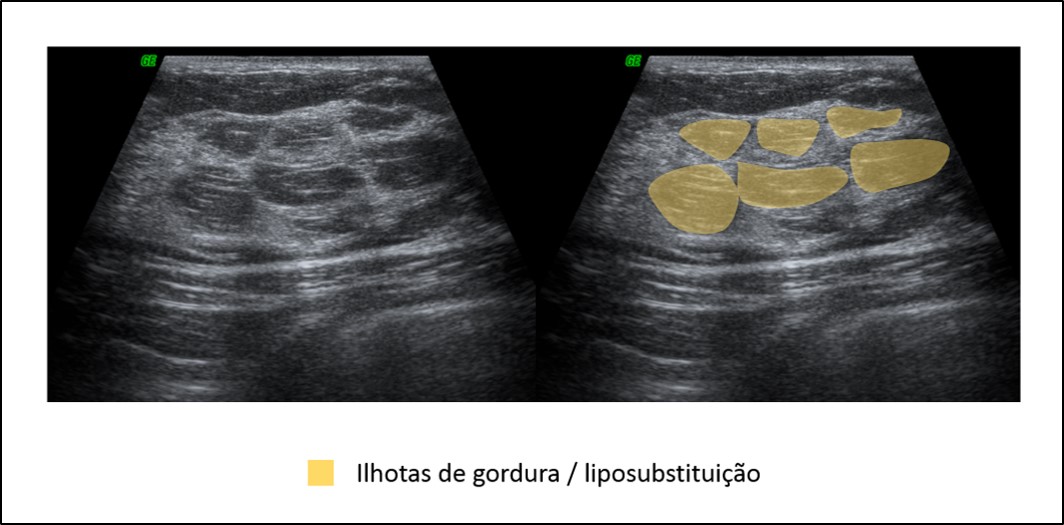

O tecido estromal fibroso interlobular apresenta, à ultrassonografia, ecotextura predominantemente hiperecóica, refletindo sua maior densidade e conteúdo colágeno. Em contraste, o tecido glandular propriamente dito — constituído pelos lóbulos — e os elementos ductais tendem a apresentar ecotextura isoecóica ou discretamente hipoecóica em relação à gordura pré-glandular.

Essa heterogeneidade ecográfica é fisiológica e decorre da íntima interposição entre estroma fibroso, unidades ducto-lobulares e tecido adiposo. O reconhecimento dessa arquitetura normal é fundamental para evitar a interpretação equivocada de áreas hipoecóicas como lesões sólidas, quando na realidade correspondem a tecido glandular normal ou ductal.

A composição tecidual da mama apresenta ampla variabilidade individual e, assim como na mamografia, essa variação também se reflete nos achados ultrassonográficos. O padrão de ecotextura observado ao ultrassom depende da proporção entre os componentes glandulares (ductos e unidades ducto-lobulares terminais) e o estroma fibroso no interior da zona fibroglandular, localizada entre a gordura subcutânea (pré-glandular) e a gordura retroglandular.

Diferentemente da mamografia — na qual tecido glandular e estroma fibroso apresentam densidades semelhantes — a ultrassonografia permite distinguir esses componentes com maior precisão: o tecido glandular e os elementos ductais tendem a apresentar ecotextura hipoecóica ou isoecóica, enquanto o estroma fibroso interlobular é tipicamente hiperecóico. Essa diferença é fundamental para a identificação de lesões verdadeiras e para a correta interpretação do parênquima de fundo.

Com base na composição tecidual predominante, descrevem-se três padrões básicos de ecotextura mamária ao ultrassom, em concordância com o BI-RADS:

Ecotextura de fundo homogênea gordurosa, na qual os lóbulos adiposos e bandas ecogênicas de sustentação predominam;

Ecotextura de fundo homogênea fibroglandular, caracterizada por uma faixa espessa e relativamente homogênea de parênquima fibroglandular sob uma camada delgada de gordura subcutânea, sendo esse o local onde se concentram a maioria das lesões mamárias;

Ecotextura de fundo heterogênea, na qual áreas de gordura isoecóica se intercalam com regiões fibroglandulares hiperecóicas, refletindo maior complexidade arquitetural do parênquima.